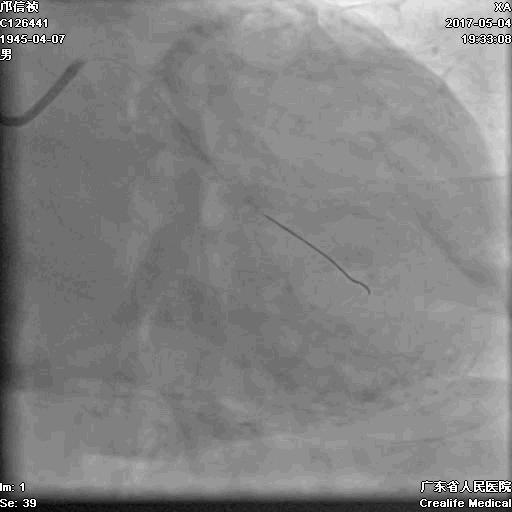

RRA:6F AL0.75 GC –RCA;

RFA:7F XB 3.5 GC—LCA 150cmcorsair

正向130cmFinecross微导管支持下尝试送PILOT150、Gaia 2导丝无法通过RCA闭塞段

SION导丝通过侧枝

逆向导丝:更换Gaia2

正向导丝:Gaia2,PILT150

正向导丝knuckle

2.5*15mm球囊扩张,逆向导丝尝试,但未能进入正向GC

1.正向2.5*15mm球囊扩张,Reverse CART

2.Guidezilla延长导管辅助下,逆向导丝进入正向GC

1.更换RG3导丝

2.GC送入普通导丝,保护LM